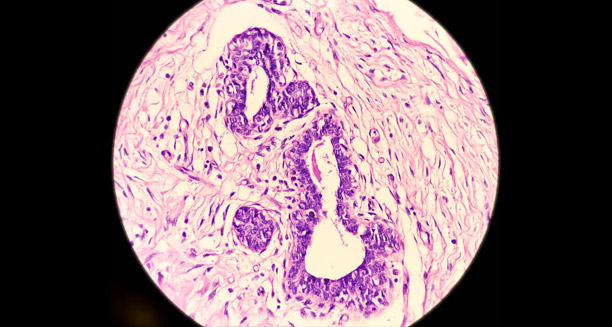

Follicular Occlusion: The Starting Point

At the core of HS is follicular occlusion, which means the hair follicle becomes blocked. In people with HS, follicles—especially in areas like the underarms, groin, buttocks, and under the breasts—get clogged with keratin or debris. This blockage traps sweat and oil inside the follicle. Eventually, the follicle bursts, releasing its contents into the surrounding skin. This triggers a strong immune response that leads to swelling, pus, abscesses, and ultimately scarring.